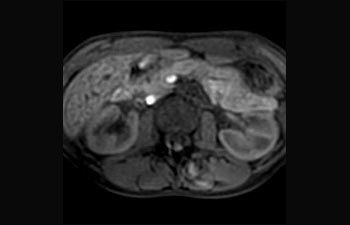

Find the right clinical applications for your needs

1 Based on an internal study comparing workflow with the Achieva MR system 2 ComforTone will be available with Prodiva 1.5T in Q4 of 2017 3 Based on an internal study comparing workflow in a mix of brain, spine, MSK and body applications with the Achieva MR system 4 Normal operation is defined as typical scanning performed with uninterrupted availability of electricity, magnet cooling and excluding service actions 5 Dependent on contract entitlement and local availability 6 Other MR refers to 60 cm 1.5T whole body MRI systems